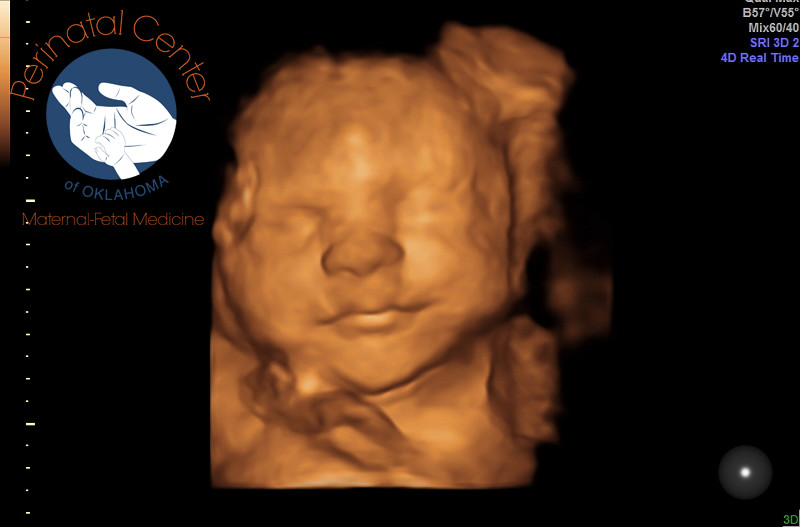

• I was about to say $80 is so cheap. In OKC it's around $180 for 3D/4D.

A Glimpse Before & After in Moore will do a 15 minute peek for $80.

• @DrillSergeantCat I actually did the sneak peek there at 12 weeks. She told me since I'm 30 weeks that option ended at 24 or 25. The cheapest the tech quoted was $160 I believe. That's only Tuesday through Friday 9-3. I work. No big deal. I'll see her (baby girl) again in a week for measurements at my OB. I love that there's a fellow OKC southsider on here :)

I've never been there. I thought about it because my insurance only covers one ultrasound, but they scheduled me for a second. It's tomorrow and since I go to a perinatologist for my ultrasounds, they do a few minutes in 3D.